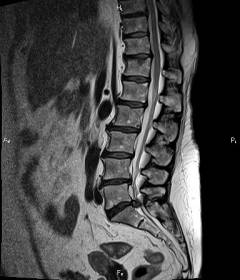

Анкилозирующий спондилит, или болезнь Бехтерева, диагностирует ревматолог. Учитываются специфические симптомы: боль и скованность в позвоночнике, усиливающиеся в покое, а также дискомфорт в грудной клетке. Для подтверждения диагноза необходимы МРТ или рентгенография позвоночника, причем МРТ более чувствителен для выявления ранних изменений. Также проводят общий анализ крови, где часто наблюдается повышение СОЭ.

Остеохондроз поясничного отдела диагностирует невролог. Диагноз ставится на основании клинических признаков: боль вдоль нерва, односторонняя атрофия мышц и нарушения чувствительности. Подтверждение диагноза осуществляется с помощью рентгенографии или МРТ, которые показывают дистрофические изменения в межпозвоночных дисках.